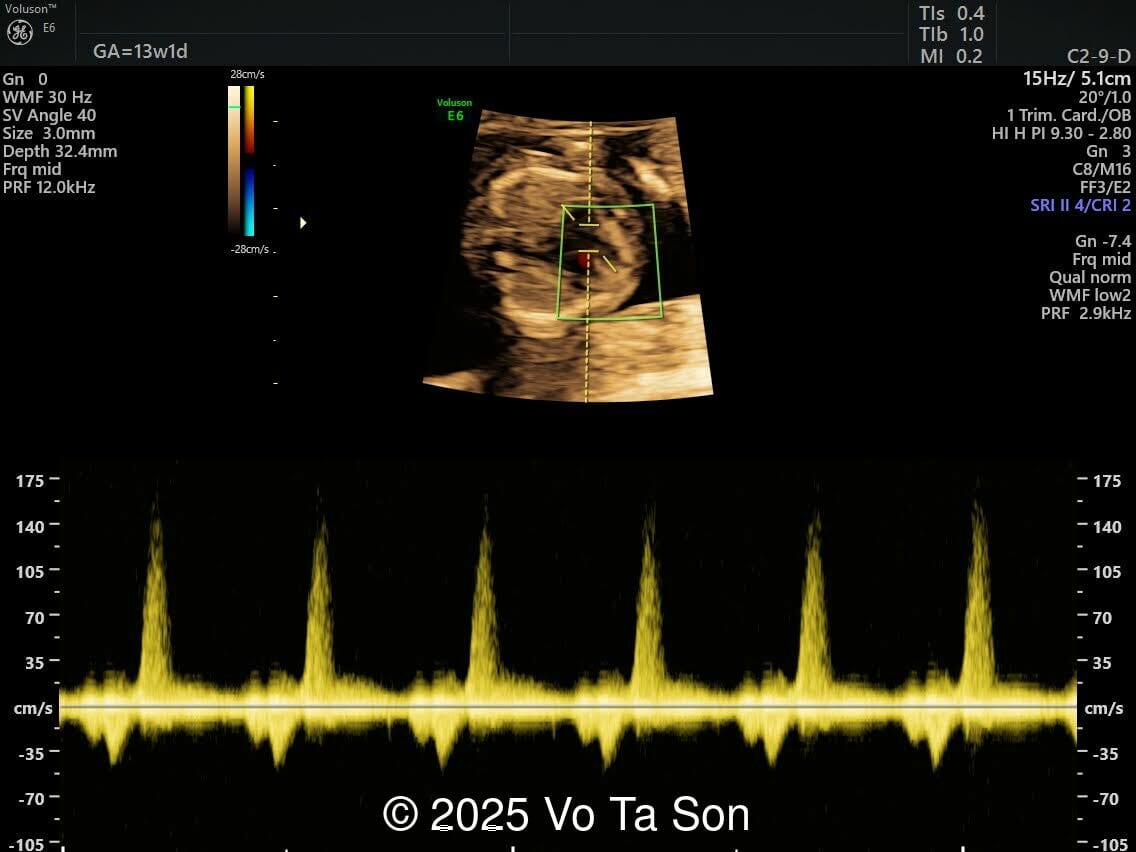

Tricuspid  flow

Image 4 Tricuspid flow

• Tricuspid valve regurgitation